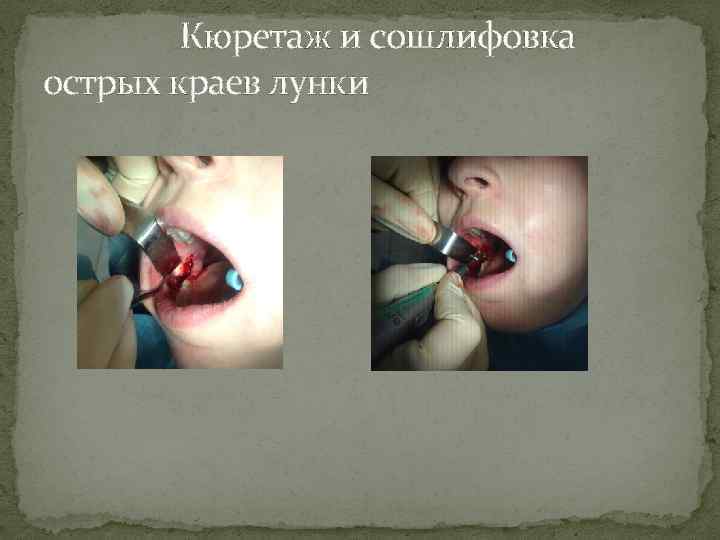

Кюретаж и сошлифовка острых краев лунки

Кюретаж и сошлифовка острых краев лунки